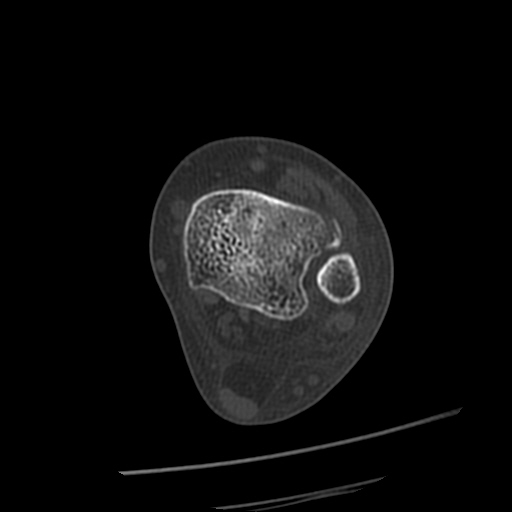

[¹ß¸ñ] distal tibiofibular ligament sprain with avulsion fracture of tibia

CT : avulsion fracture of distal tibia at distal tibiofibulat ligament insertion.